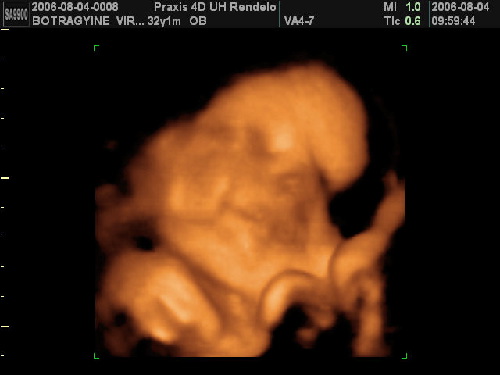

Képek pedig tüneményesek!